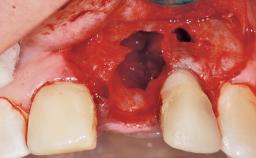

A 30-year-old female patient had lost tooth 21 and was referred to our clinic for consultation and treatment. Due to advanced apical infection, tooth 21 had been extracted two months earlier at another clinic and an acrylic-resin tooth had been bonded to the adjacent teeth. The patient desired implant treatment to avoid any damage to the adjacent natural teeth. While the patient had no history of any systemic disorder, she was a heavy smoker and exhibited medium to advanced periodontitis in the entire jaw. After the initial treatment to achieve a pocket probing depth of less than 4 mm and no bleeding on probing, a decrease in the height of the papillae mesial and distal to the extraction site and overall gingival recession were observed.

| Bone Augmentation | Horizontal|Staged |

| Augmentation Materials | Autogenous chips|Membrane |

| Bone Volume | Deficient horizontally, requiring prior grafting |